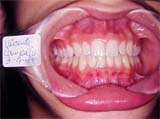

Fig. 2

Vista frontal da oclusão deste paciente, onde observamos o desvio dentário acompanhando o desvio facial. O mordida invertida dos elementos 13/43, geraram um fenômeno de adaptação excepcional. A ausência de bossa canina do elemento 13, por falta de função e o aparecimento de bossa canina no elemento 43 por excesso de estímulo.